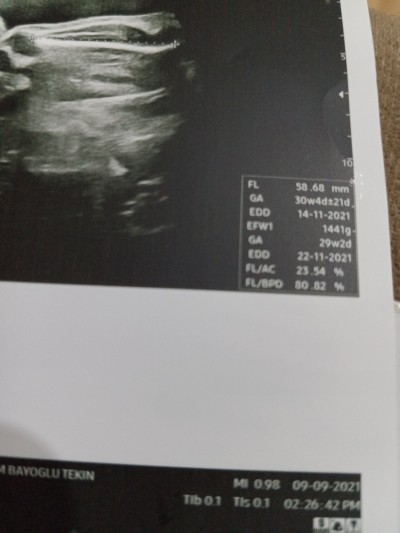

Kızlar burdan bebeğin boyunu anlayan varmı?

30+2

Canım uydurdun demedim evet dopru öyle yazıyor ama o rakam bişeyle çarpılıp asıl boyu çıkıyo ortaya onu demek istedim.ortama bebekler zaten 50-52 cm doğuyor.30 haftada 58 cm olmaz yani

FL'yi 7 ile carpinca boyunu buluyorsn canm

41cm canım boyu